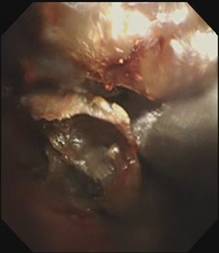

时间紧迫,每一秒都关乎生命,患者立即被送到内镜室,支气管镜检查的结果令人触目惊心:患者的总气管被痰痂、血痂、痰栓等物几乎完全堵死,仅残留一丝细小的通气通道,那是生命最后的脆弱纽带!

在紧张且充满紧迫感的抢救氛围中,呼吸介入团队成员默契配合,在支气管镜下使用异物钳夹取、超低温冷冻等方法清除异物。

随着每一次精准夹取和冷冻操作,顽固的异物被一点点从狭窄的气道内剥离出来,堆积在一旁的痰痂、血痂和痰栓逐渐增多,堆积起来的长度居然达到了惊人的18厘米。

当最后一块异物被取出,患者的气管终于露出了原来的“庐山真面目”: